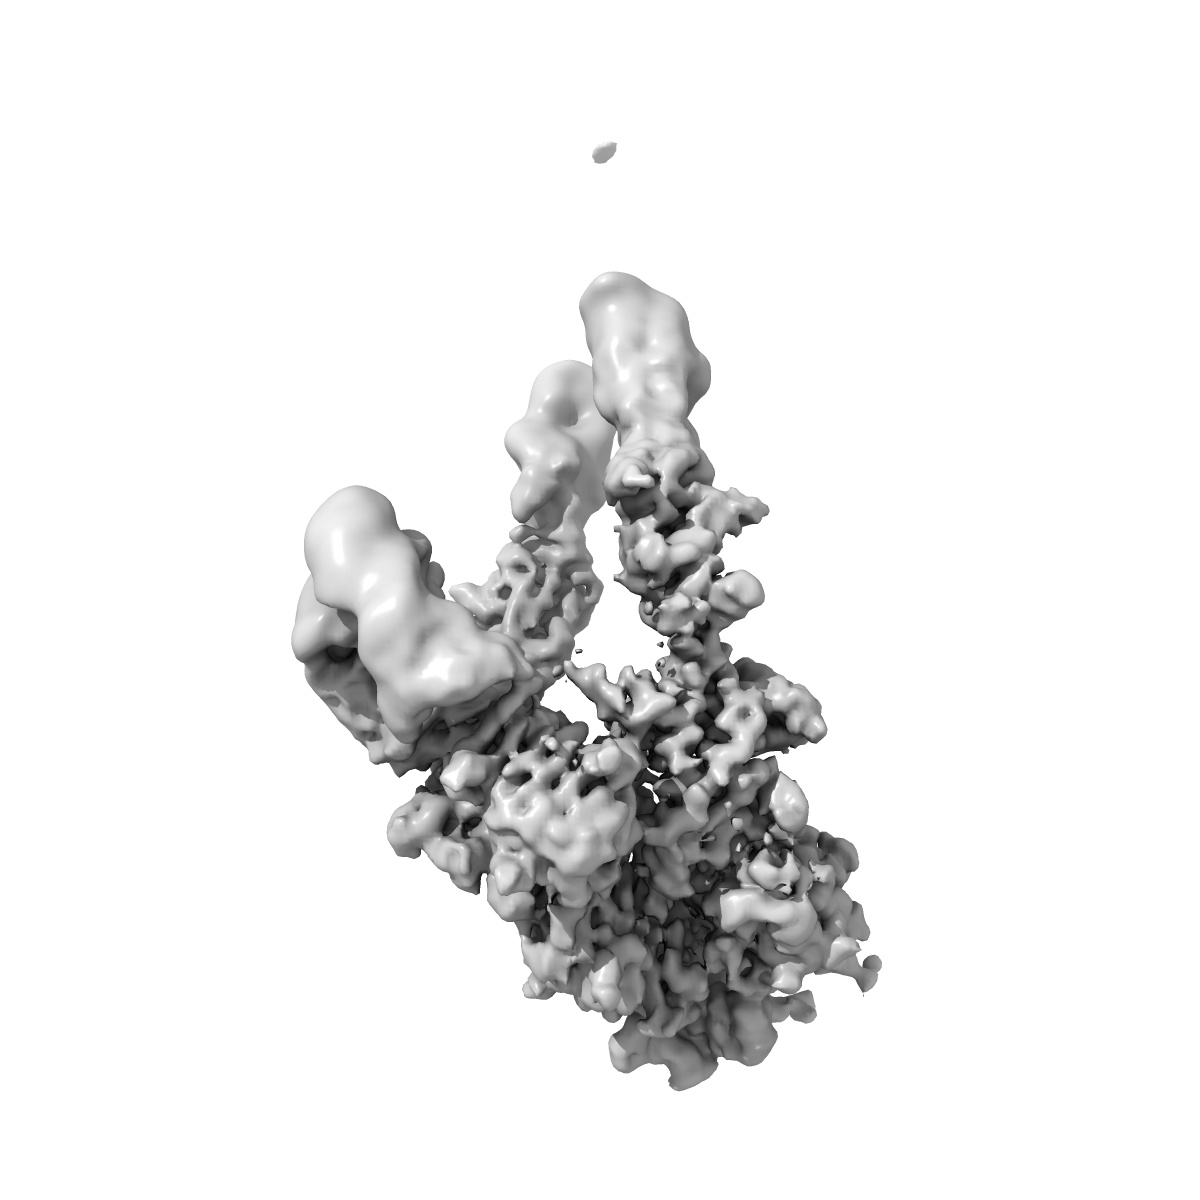

Cryo-EM structure of short form insulin receptor (IR-A) with three IGF2 bound, asymmetric conformation.

Single-particle3.8 Å

Sample: Short form insulin receptor (IR-A) with three IGF2 bound, asymmetric conformation.

Fitted models: 8vjc